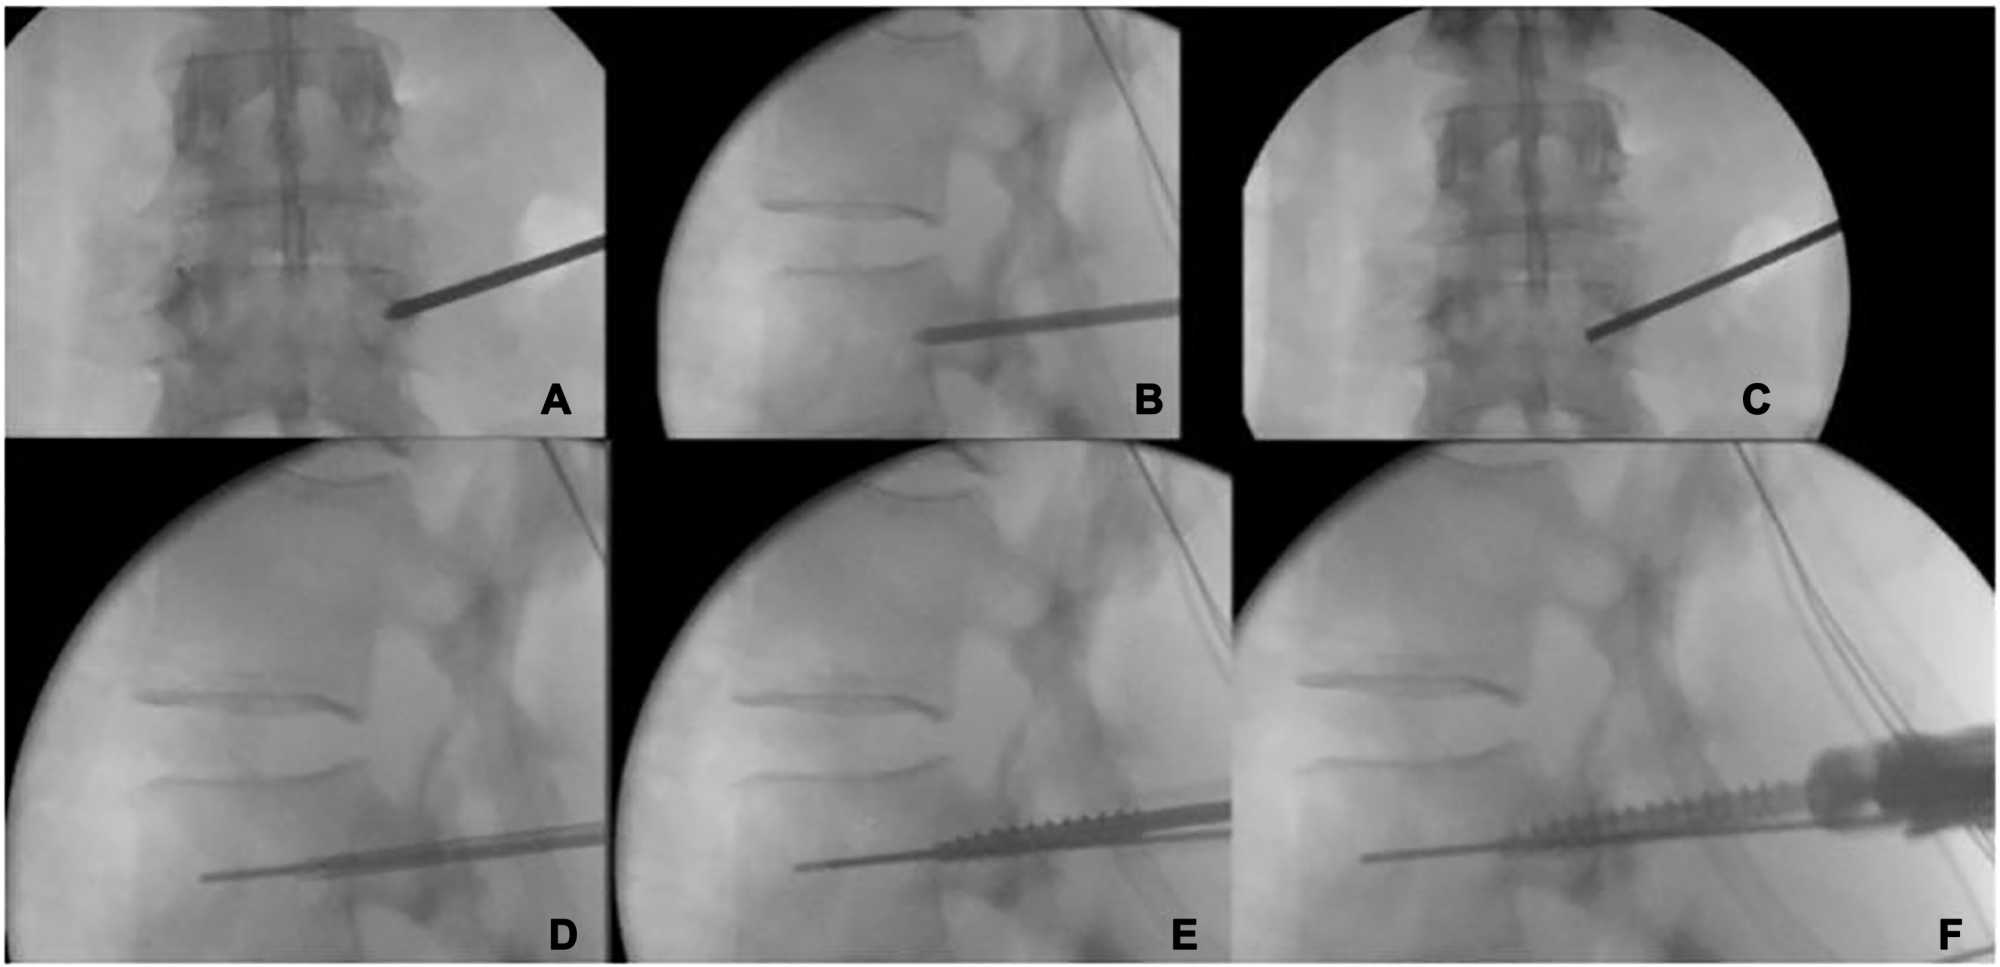

3. Steps of the Surgical Technique (Figure 1) [16]

• Surgical intervention was carried out on a radiolucent table (a Jackson frame), in the prone position, and under general anaesthesia.

• Percutaneous minimally invasive pedicle screw insertion was done fluoroscopy assisted.

• Accurate real anteroposterior (AP) & lateral views of the targeted vertebrae must be Carried out to localize the true image and true entry point.

• Local anaesthesia was given, & one cm of the lateral skin was incised to access the pedicle after accurate localization of the pedicle (Larger skin incisions are necessary for older instruments).

• The facial incision must be broader in diameter than the incision made on the skin.

• Following this, a Jamshidi needle is inserted via the entry point, which is ideally positioned at the intersection of the transverse process & articular facet.

• The entry points for the right & left pedicles must be between 2 & 3 o’clock also 9 & 10 o’clock, respectively.

• The Jamshidi needle is subsequently inserted into the pedicle while managing the AP & lateral views.

• On the lateral view, the Jamshidi needle must have reached the midpoint of the pedicle by the time it reaches that position on the AP view.

• The needle tip shouldn’t come in contact with the inner border of the pedicle on the AP view when it reaches the posterior border of the vertebral body on the lateral radiograph.

• The guide wire is introduced into the vertebral body via the Jamshidi needle, ensuring that it doesn’t traverse the anterior cortex, which could result in damage to the greater vessels.

• The Jamshidi needle is then eliminated without removing the wire.

• Kocher clamp is used to retract the guide wire.

• Following the insertion of the screws, the guide wire is extracted subsequently to the pedicle screw’s tip traversing the vertebral body’s posterior border as seen on the lateral radiograph.

• Bending the guide wire while pressing can be dangerous &inserting the screw, like doing so, could cause the guide wire to break. In order to prevent this complication, it is imperative to eliminate the guide wire promptly upon the screw tip penetrating the vertebral body through the posterior vertebral wall.

• Rods are applied and locked in place after the insertion of all desired screws.

• For construct control, final AP & lateral imaging must be performed.

• Post-operative antibiotics and Painkillers (acetaminophen and NSAIDs) were given for two days.

• Most patients were discharged on the 2nd post-operative day [16].

Figure 1. A fluoroscopic technique for inserting screws has been explained. (A) Point of entry for AP fluoroscopy; (B, C) Permission for the Jamshidi needle to make contact with the inner pedicle border on the AP image; (B, C) Specifically, once the needle passes through the spinal body’s posterior wall. (D) Subsequently, the guide wire is introduced into the cannula while exercising caution to avoid traversing the anterior wall of the vertebral body. (E) Taping is performed on all guidewires with utmost care to prevent their removal. (F) Following screw insertion, the guidewire can be extracted once the screw tip contacts the posterior vertebral wall.